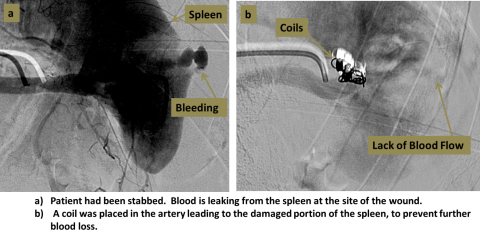

Two step diagram of embolization process. A. Showing a spleen and bleeding. B. Showing the placing of a coil in the artery leading to the damaged portion of the spleen, to prevent further blood loss.

An interventional radiologist accesses the femoral artery at the groin. Small catheters and wires are used to navigate into the chosen artery, confirmed with angiography. An occluding substance can then be injected, or small coils can be placed into the artery to block the vessel.

Embolization procedures allow blockage of blood vessels without invasive surgery. Embolization can be used to stop arterial bleeding, and can also be used to block blood vessels for other reasons, such as to treat tumors, shrink vascular malformations, or re-direct flow.